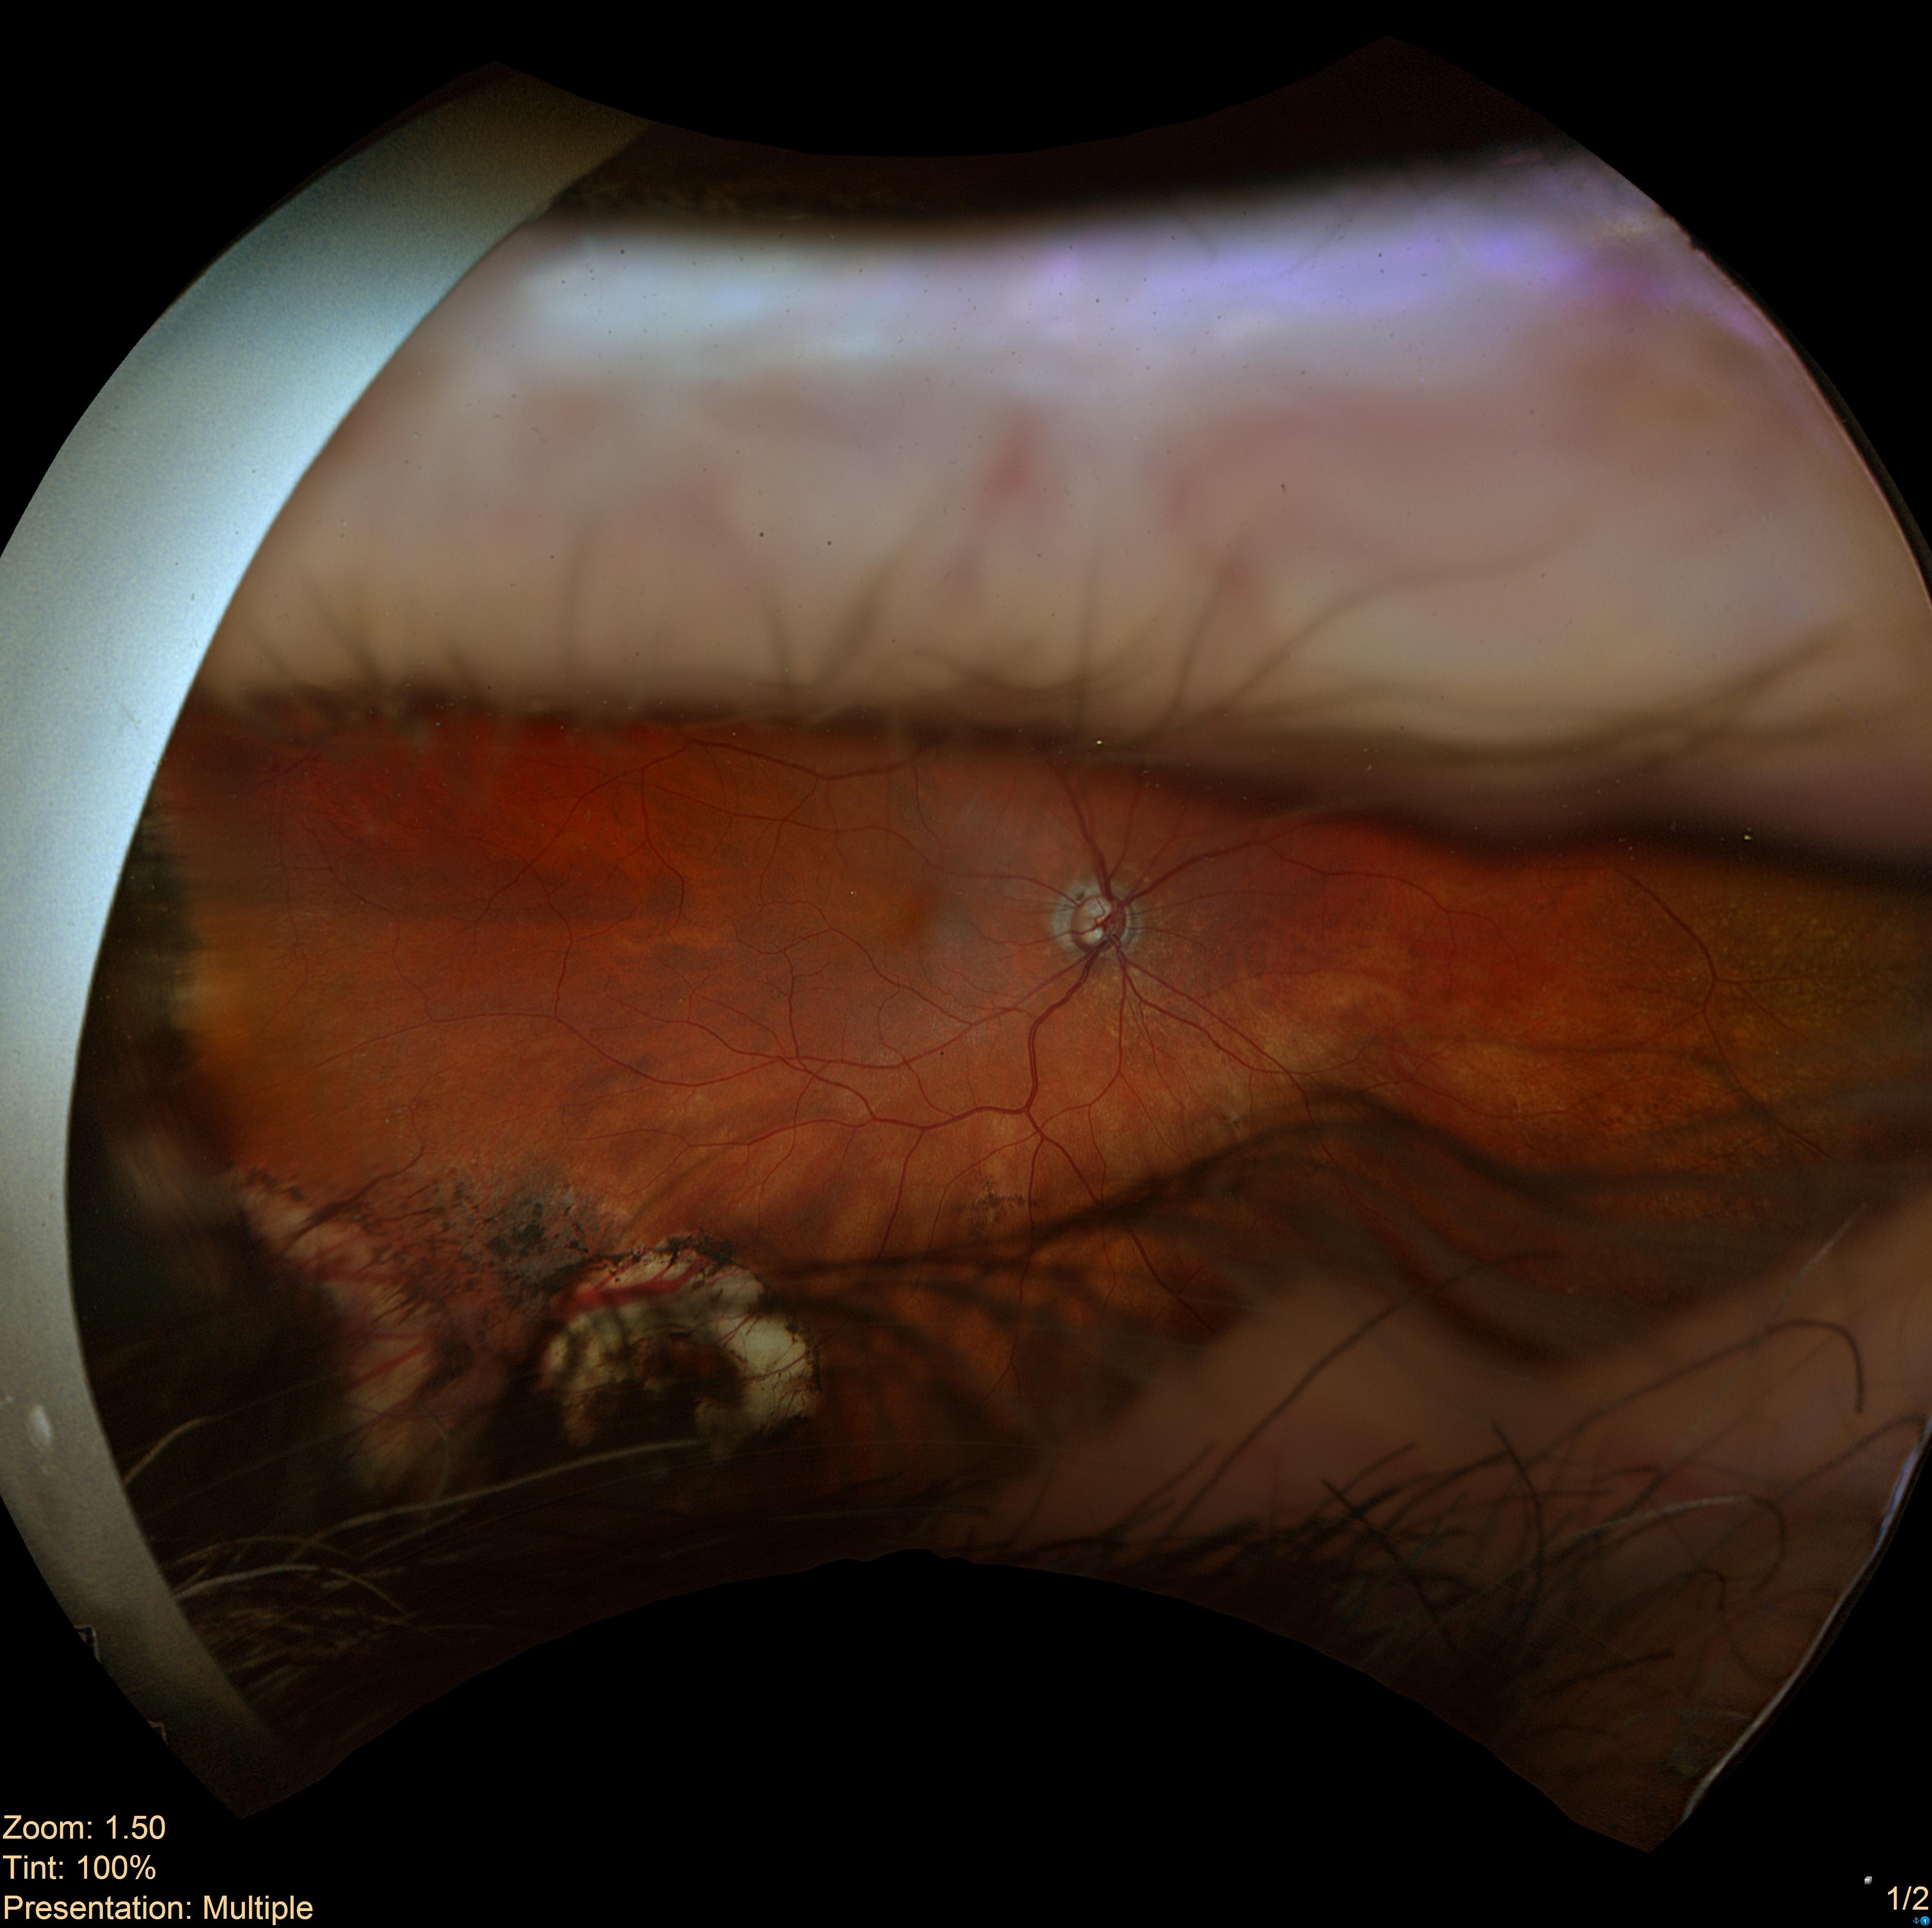

Starting with a fundus photo (Image 1), the AI identifies and maps retinal blood vessels (Image 2).

In image segmentation, AI learns to classify different pixels on a picture, based on what it represents.From there, we calculate a Tortuosity Score, a numerical value representing vessel curvature and complexity.

For example, a score of 1.21 quantifies the degree of twisting or bending within the vessels. Tracking this score over time could reveal subtle vascular changes before a clinical event occurs.